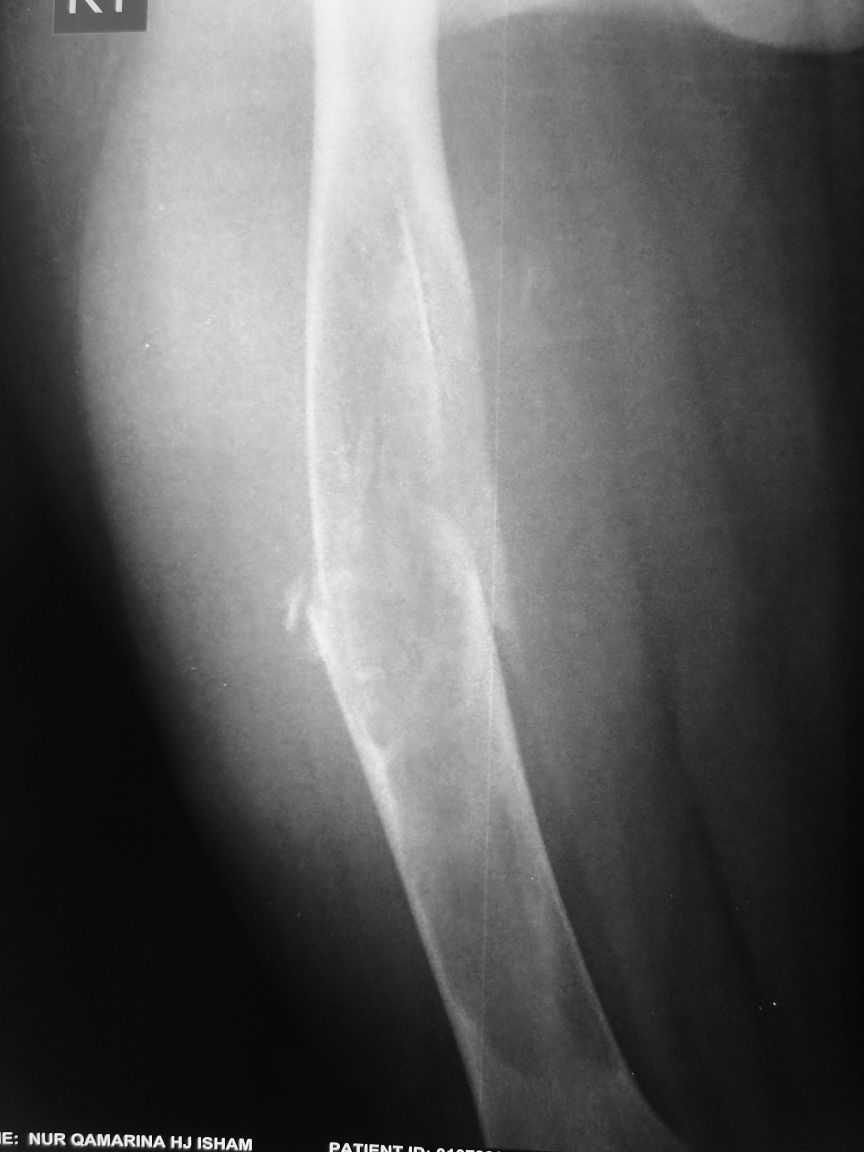

Re: Pathological fracture femur

Most likely fibrous dysplasia, we had the same case but younger age patient 4 years ago treated by uniplanar ext fix followed by percut. curretage and bone marrow injection and healed well.

at this age IMN can solve the problem .

I agree that this case is fibrous dysplasia.

As a method of treetment I propose removal of fibous tissue and cavity allografting, including frozen cortical long graft as an intramedullary nailing. I think it is a good decision without using of any metal construction.